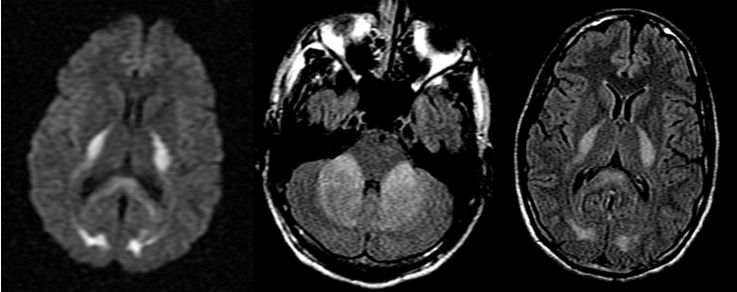

男,29岁,言语不清,协调不良以及行走不平衡3周。

答案:*洛因海**海绵状白质脑病。*洛因海**海绵状白质脑病(heroin spongiform leukoencephalopathy,HSLE)是因烫吸或静脉注射*洛因海**而引起的中枢神经系统器质性疾病。临床和影像特点如下:

1. 有吸*洛因海**史;

2. 急性或亚急性起病;

3. 小脑受损为首发症状,进一步加重可出现锥体系及锥体外系受损表现,甚至昏迷、去皮层态势,但感觉系统不受累;

4. CT和MRI影像显示病灶位于脑白质区,呈广泛、对侧性损害(小脑半球、脑干、内囊后肢、胼胝体压部及大脑半球后2/3),其中小脑受累严重,小脑中线两旁、边界清楚的对侧性类圆形或蝴蝶样病灶最具特点(蝶翼征);在脑干部位,若同时有红核及网状结构受累,则可见“蟹钳征”;在内囊后肢则呈“八字征”。病变在T1W为低信号,T2WI为高信号,FLAIR为高信号,且增强扫描一般无强化.5.病理显示脑白质空泡样变。